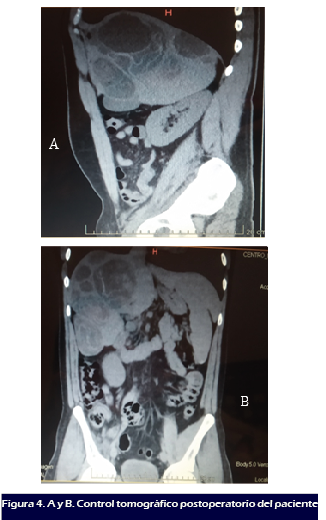

Paciente evoluciona satisfactoriamente. En postquirúrgico

inmediato fue ingresado en Unidad de cuidado Intensivo (UCI) durante 3

días, con seguimiento del servicio de infectología y

epidemiología, bajo el tratamiento de albendazol 800mg

vía oral (VO) diario por 3 meses + praziquantel 1200mg VO,

dexametasona 8mg vía endovenosa (EV). Es egresado al

séptimo (07) día de hospitalización en buenas

condiciones generales, con tratamiento médico de albendazol, y

control tomográfico posterior al acto quirúrgico,

realizado a los 7 meses, donde no se evidencia el quiste anteriormente

reportado en retroperitoneo. La biopsia confirmó el diagnostico

de hidatidosis. (

Figura 4).